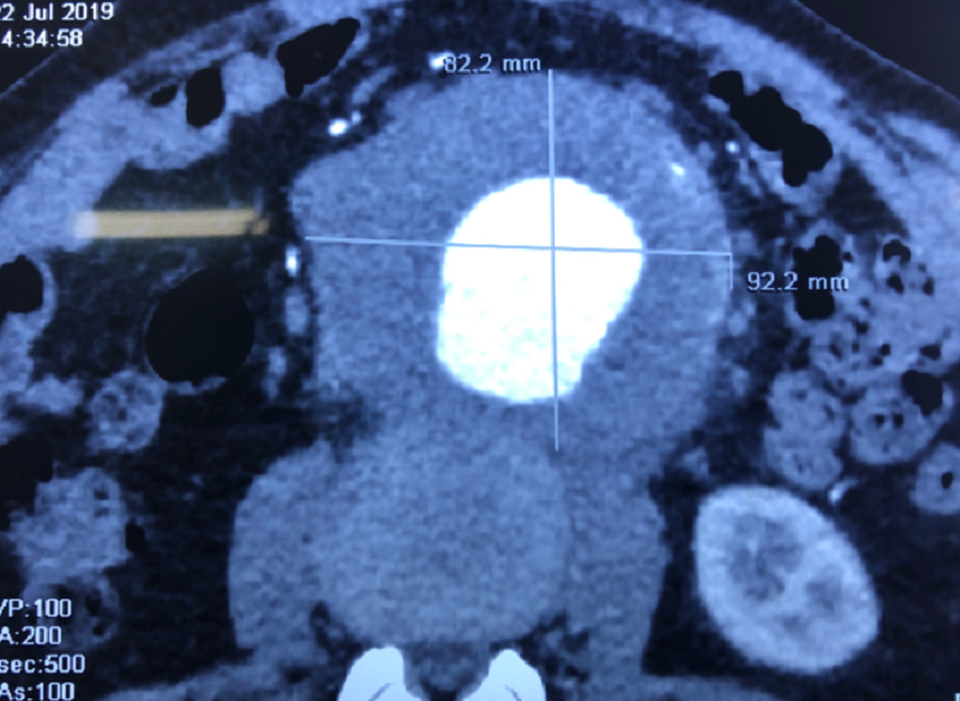

Tại đây, bác sĩ kiểm tra và xác định túi phình động mạch chủ bụng của ông người bệnh có kích thước 9cm x 8,6cm. Túi phình như một trái bưởi nhỏ, nếu vỡ sẽ khiến máu tràn vào ổ bụng gây mất máu cấp, nguy cơ tử vong lên đến trên 90%.

Quan sát phim chụp MSCT cản quang, các bác sĩ đánh giá đây là ca phẫu thuật nhiều thách thức. Khối phình động mạch chủ bụng không chỉ choán chỗ trong ổ bụng mà còn có phản ứng viêm dính vào đốt sống thắt lưng (đốt sống L1, L2) gây đau lưng. Mặt khác cổ túi phình nằm quá sát động mạch dưới thận, gây bất lợi cho thao thác phẫu thuật.